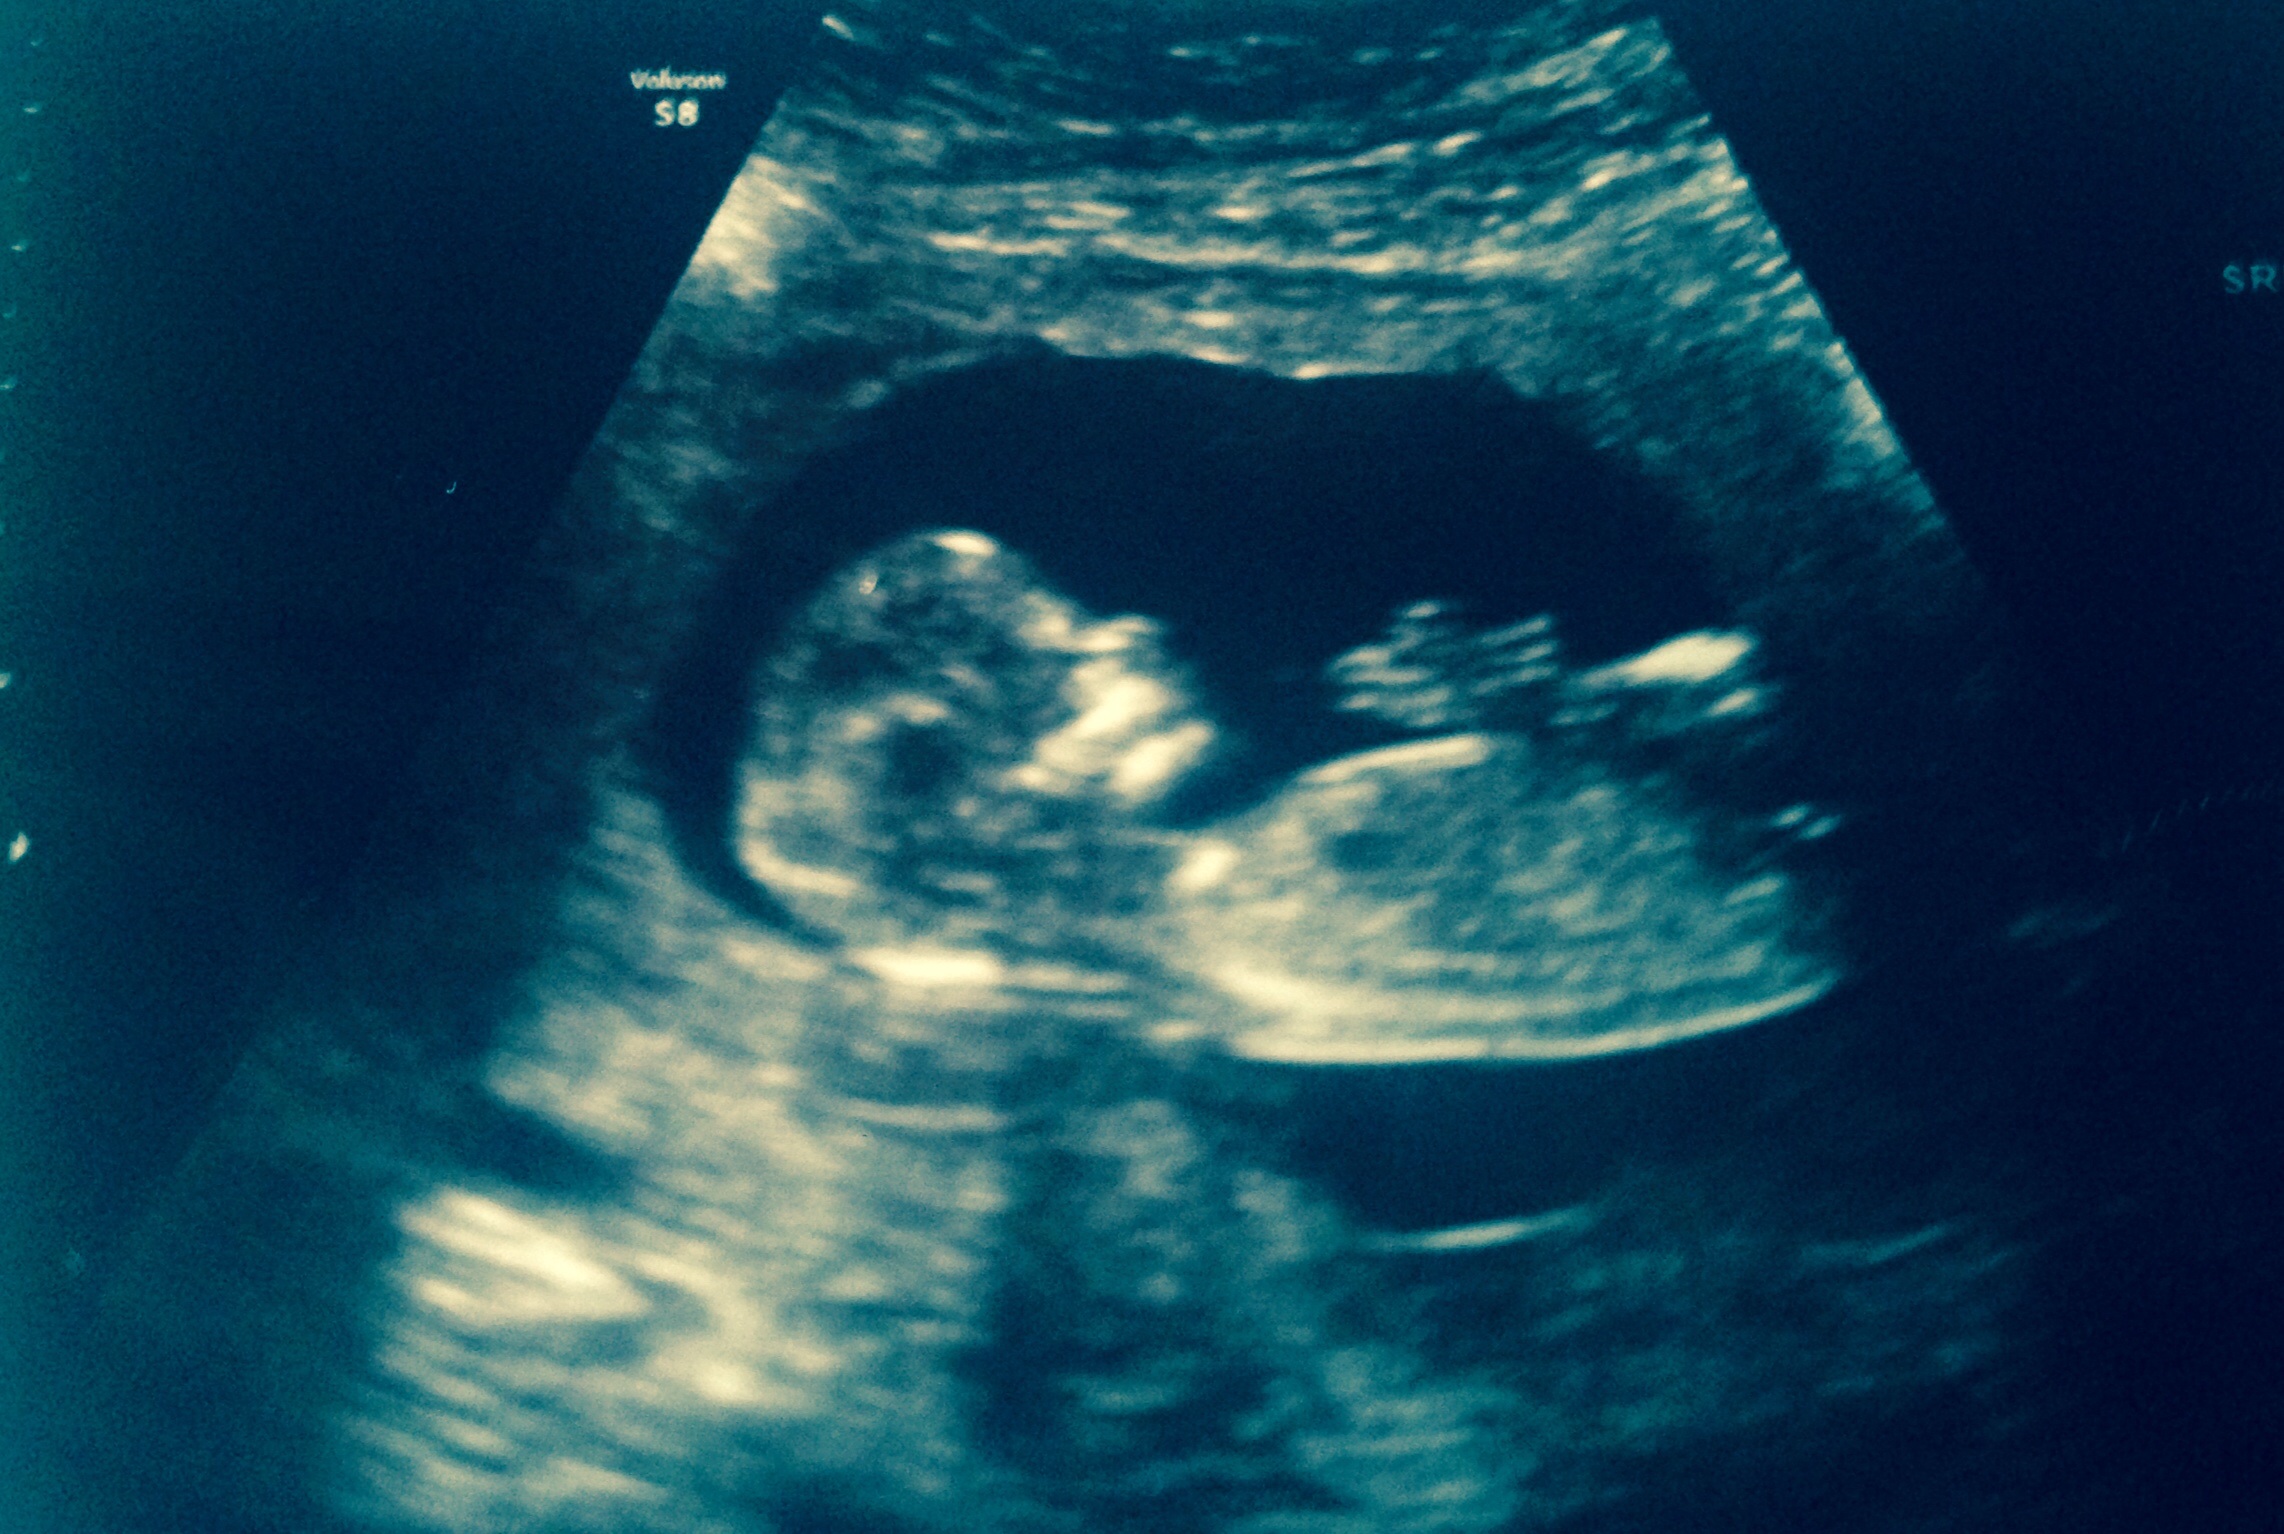

Hello I had my scan yesterday at 13+3days I was wondering if you could take a guess please.

Also I have a few questions can a boy nub turn into a girl and vice verser? I honestly have no clue about "nubs" so I have no idea how it works. Attachment 15125Attachment 15125